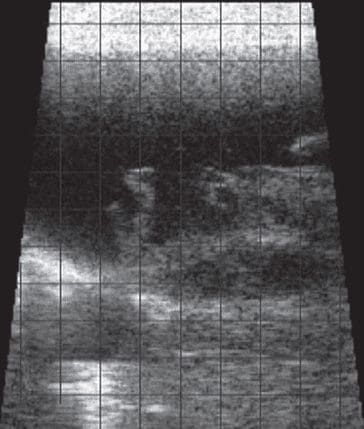

4 – Sheep with fibrinous pleuritis

Figure 4 shows a sheep with fibrinous pleuritis. This is visualized as the presence of hypoechoic fluid within the thoracic cavity containing strands/aggregates of more hyperechoic material.